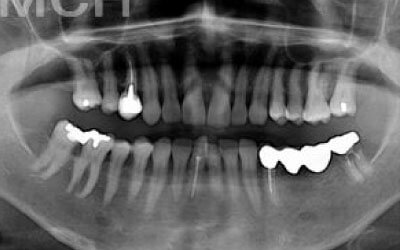

ブリッジとインプラントでは、周りの歯の寿命に大きな違いがあります。ブリッジは支えとなる歯を健康でもかなり削らなければならず、さらに噛む力が約1.5倍かかるため、その歯の寿命が短くなってしまいます。実際のデータでは、ブリッジの支えとなった歯の68%が10年以内に抜歯に至っています。

ブリッジ治療の場合も、失った歯にかかっていた力を前後の歯が支えるため、結果として残っている歯には、通常の1.5〜2倍ほどの負荷がかかってしまいます。

ブリッジなどの治療では、前後の歯を大きく削らなければならず、場合によっては虫歯でなくても神経を抜くことがあります。神経を抜いて被せ物をすると、その歯は一気に寿命の終わりに近づいてしまうのです。

最も大きな違いは、前後の歯の寿命に影響を与えることです。

ブリッジでは、抜けた歯の前後の歯を大きな虫歯と同じくらいまで削らなければならず、

また、抜けた歯の代わりに前後の歯がその力を支えるため、常に1.5倍の負荷がかかります。

1)ブリッジ

2)歯を大きく削る+支えの歯に1.5倍の力がかかる

3)前後の歯の寿命が著しく減る

ブリッジの支えの歯は、データでは10年以内に68%が抜歯になります。